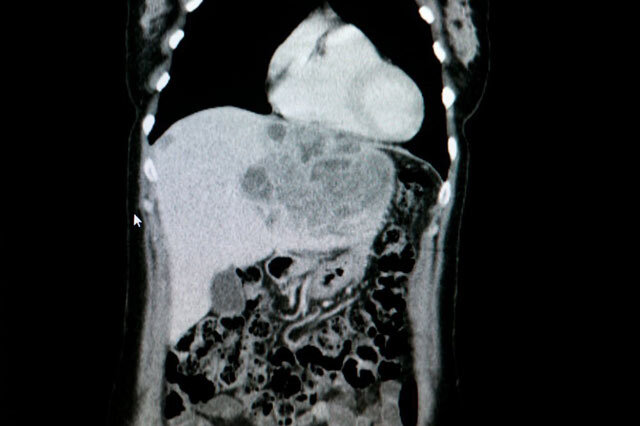

간암은 초기에 발견하지 못하면 예후가 좋지 않기 때문에 주기적인 검사가 필수다. 간암을 진단하려면 간 기능 혈액검사와 간암종양지표(AFP) 검사 및 초음파, CT(컴퓨터단층촬영) 등으로 선별검사를 시행한다. 만성간염이나 간경변증을 가진 환자는 주기적으로 간 전문의에게 진료를 받아야 한다. 간염이나 간경변증이 있는 위험군 환자는 6개월 간격으로 간암종양지표 검사와 초음파 검사를 시행해 간암을 조기에 발견하려는 노력이 필요하다.

남순우 교수는 “일반적으로 만성간염이나 간경변증이 없는 상태에서 간암이 발생하는 경우는 매우 드물다. 위험요소를 가진 환자들은 간암에 대한 적극적인 선별검사가 매우 중요하다”며 “만약 간경변증이 심하거나 위험요소가 더 큰 환자들은 더 자주 검사하거나 복부 CT를 촬영하기도 한다. 초음파로 간 실질 내에 새로운 병변이 생겼는지를 확인하고 종양지표검사가 정상으로 유지되는지를 주기적으로 확인해야 한다”고 강조했다.